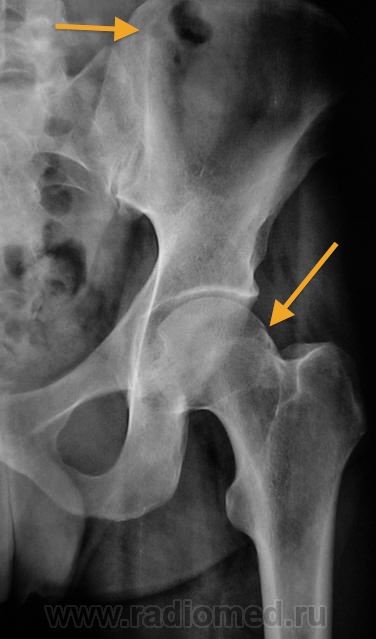

Рентгеновские снимки: Синовит тазобедренного сустава